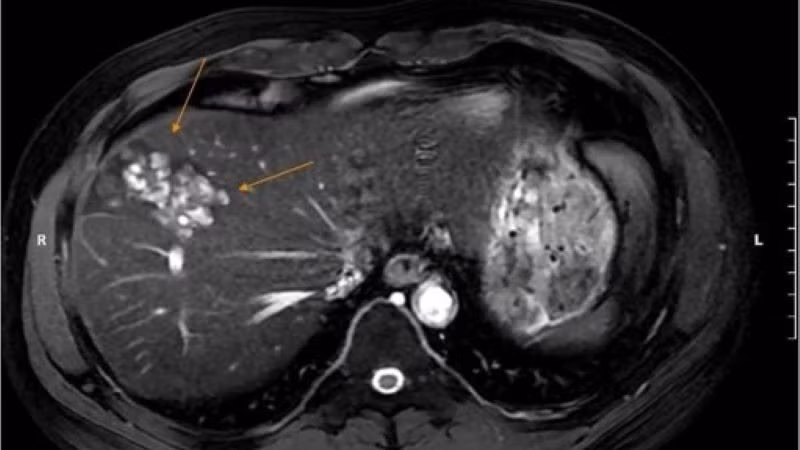

Hình ảnh tổn thương do sán lá gan.

Kết quả xét nghiệm của bệnh nhân phát hiện chỉ số bạch cầu ái toan tăng cao, cùng nhiều bất thường như rối loạn chuyển hóa lipid máu, đồng thời men gan, đường máu, mỡ máu đều vượt ngưỡng. Hình ảnh siêu âm ghi nhận gan phải có cấu trúc bất thường, nốt vôi hóa và thoái hóa mỡ độ I.

Để làm rõ chẩn đoán, bác sĩ chỉ định anh N. chụp cộng hưởng từ (MRI) ổ bụng, kết quả phát hiện nhiều ổ tổn thương khu trú gan phải, dạng hoại tử dịch hóa nhiều ổ, nghi ngờ do ký sinh trùng. Đồng thời, xét nghiệm chuyên sâu xác nhận dương tính với sán lá gan lớn và giun lươn.